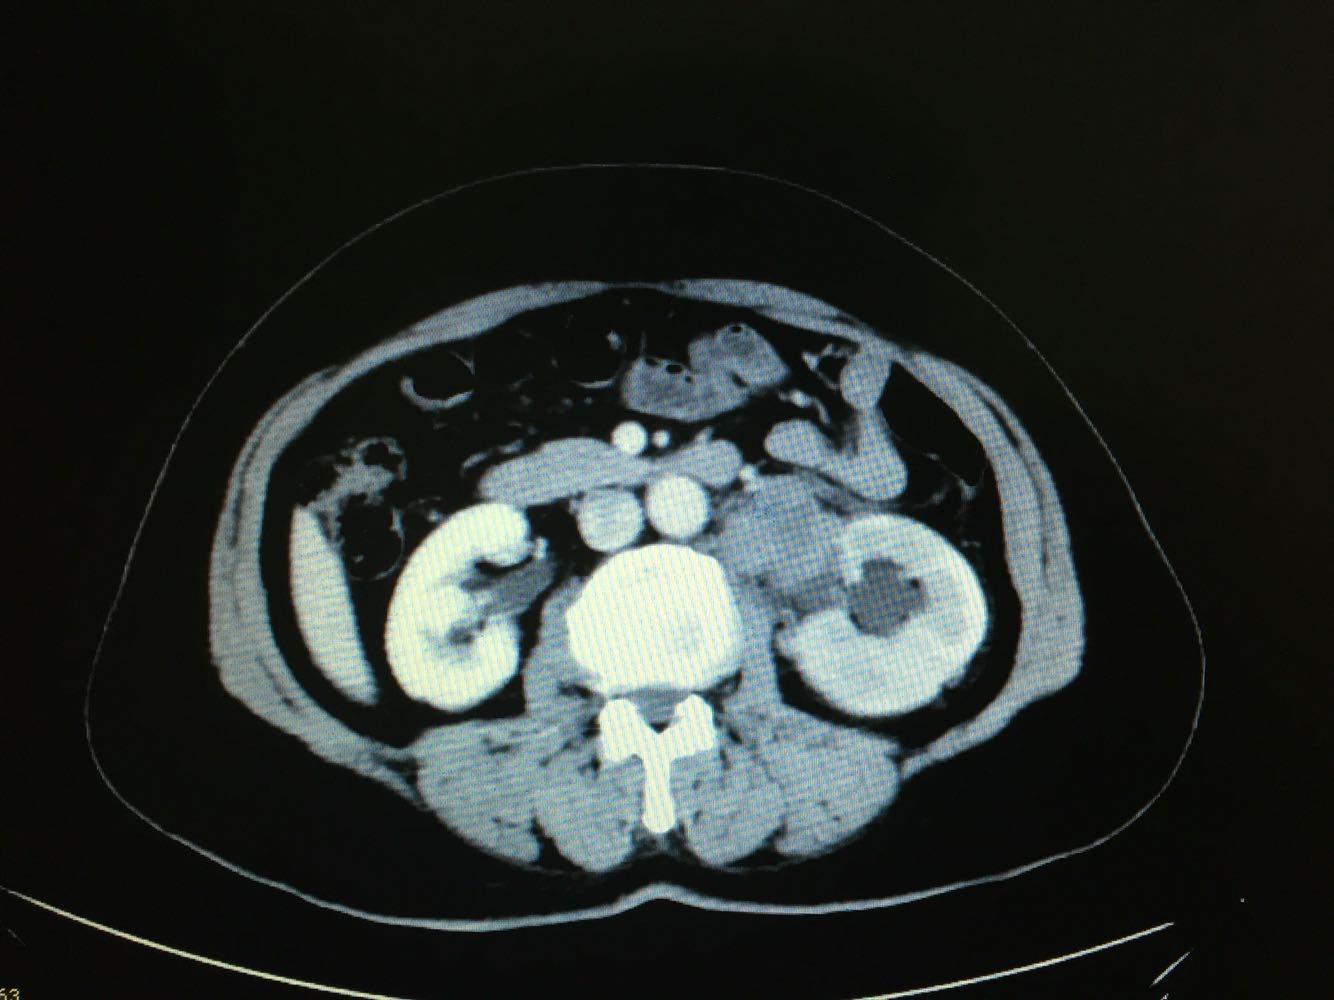

CT提示,左侧肾门处雪人样占位,包裹左肾静脉,左肾积水,与胰腺及左肾关系密切,血常规,肝肾功未见明显异常,GFR左侧27,右侧58。

诊断,左侧腹膜后占位:淋巴瘤?或者淋巴样增生?,侵犯周围器官组织?